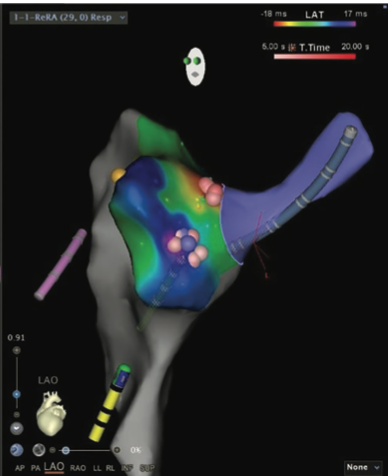

Supraventricular tachycardias (SVT) are common arrhythmias that can be a source of significant palpitations. Radiofrequency ablation is commonly performed in these patients, with a very high success rate of 95%. For a safe and successful ablation, a thorough electrophysiological evaluation of the arrhythmia is performed before attempted ablation. Various observations noted during sinus rhythm as well as during tachycardia can provide clues to the mechanism of the tachycardia. Ventricular overdrive pacing (VOP) is commonly performed during narrow complex tachycardia, and the postpacing response and postpacing interval (PPI) can provide a diagnosis of the type of SVT. A response of V-A-V is noted in AV node reentry (AVNRT) and AV reentry (AVRT), and a V-A-A-V response is consistent with the diagnosis of atrial tachycardia (AT).1 Herein, we present an interesting case of an atrial tachycardia with a short VA interval and V-A-V response noted on ventricular overdrive pacing. We discuss possible mechanisms of V-A-V response in this patient and why we believe it was a pseudo V-A-V response.